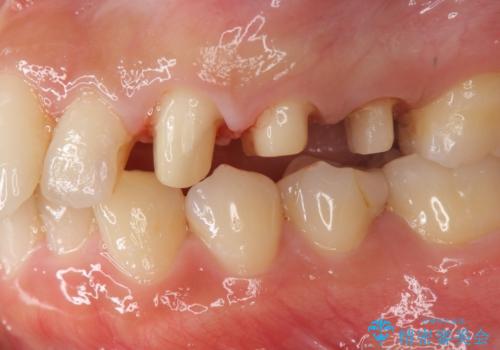

挺出小矯正を行った縁下カリエス治療

- 治療途中で虫歯治療を放置し、違和感が強くなってきたためしっかりとした虫歯治療を行いたいと希望され来院されました。

X線撮影を行い、隣接面に多発した虫歯と歯ぐきよりも深くなってしまった虫歯を小矯正をおこなったのちのセラミック治療で問題を解決します。